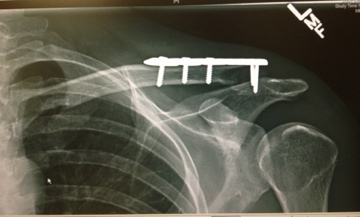

Recovery continues to go well. I saw the surgeon a few days ago and got a new set of X-rays. I’m still doing some pretty simple exercises for physiotherapy. More aggressive exercises will have to wait because the torn ligaments simply need time to repair. One worry is that because I don’t have much fat on my shoulder the plate will rub against my skin when I run and cause discomfort. The solution is to remove the plate, although that has to wait at least 6 months. Other than that I should be able to run normally with the plate.

I got screwed.

Dr. Moro (highly regarded surgeon I was lucky to get hooked-up with) went over my X-rays with me and told me about the different options. Seeing that there was a 26mm gap between the two parts of my clavicle, he suggested that a plate be inserted to ensure the bone joins again. The main part of my clavicle was much higher than usual because I ripped the ligaments that hold it in place. Luckily a bed was available later that afternoon and I was able to go under the knife that evening.

here you can see the shoulder on the right, my left shoulder, has a break.